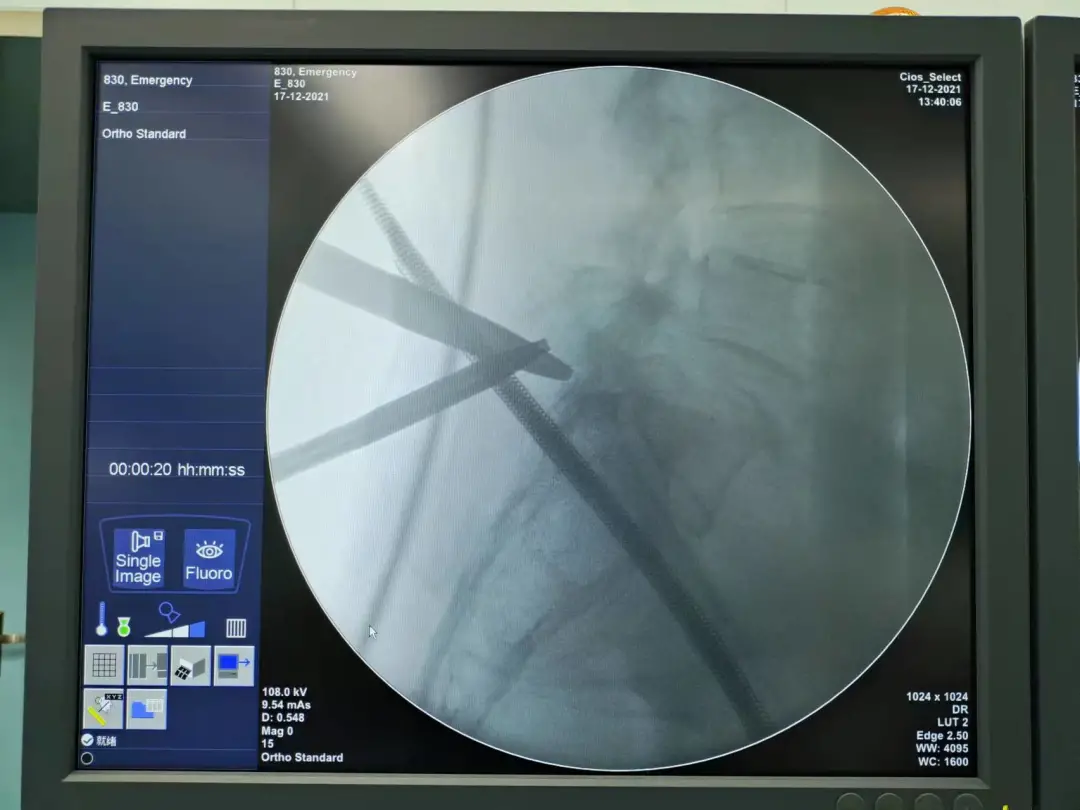

完善术前相关检查后,12月17日,肖林团队为李女士施术,以UBE技术成功扩宽了腰椎管,手术无血。术后,李女士腰腿疼痛缓解明显。

肖林正在为李女士清理腰椎管

术后,腰椎管狭窄改善